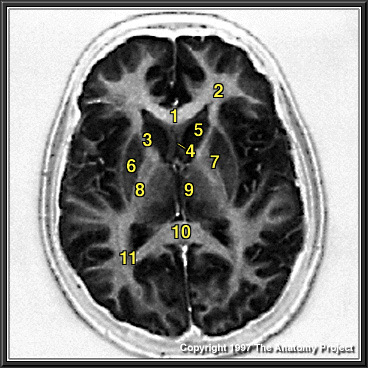

N1A5P7

Thomas R. Gest, PhD